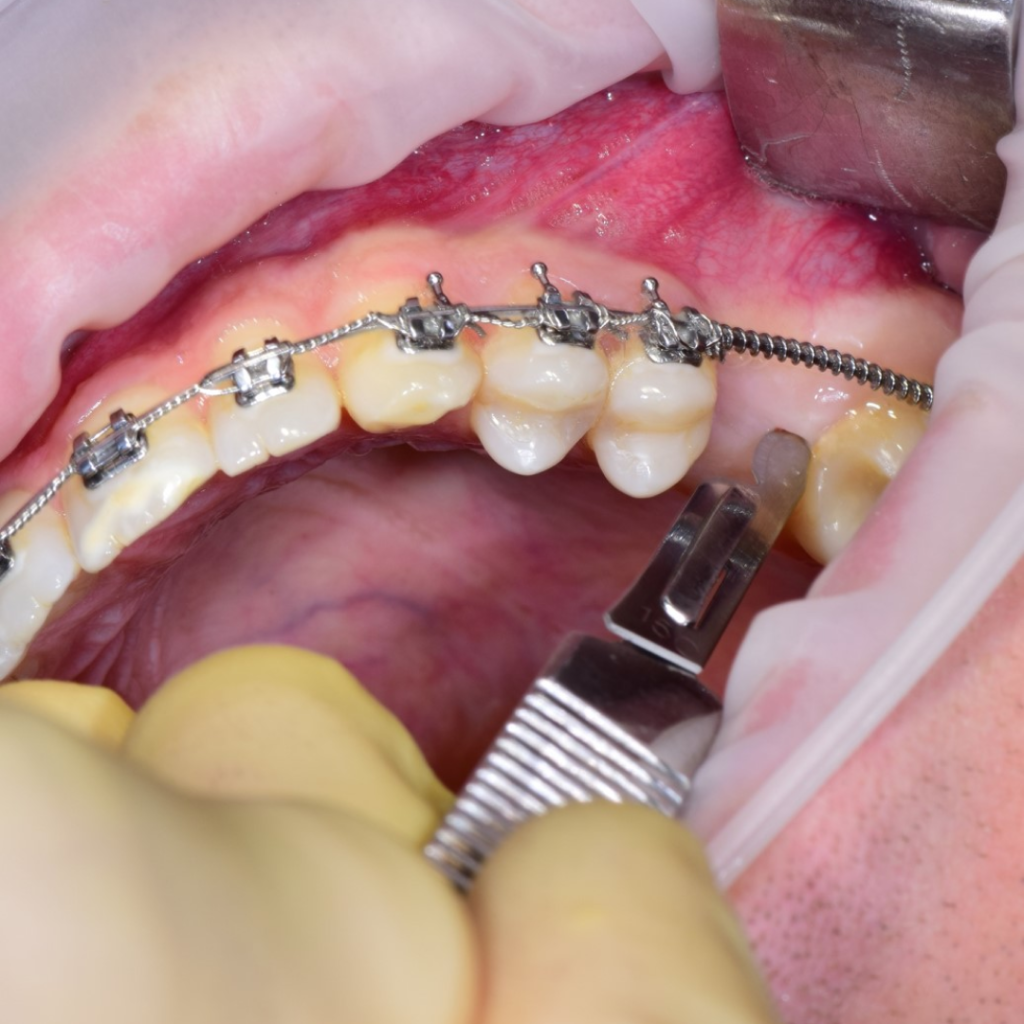

По результатам диагностики принято решение провести синус-лифтинг с помощью боров SinPro. В ходе вмешательства установлены имплантаты AnyRidge и AnyOne с первичной стабилизацией 40 Ncm.